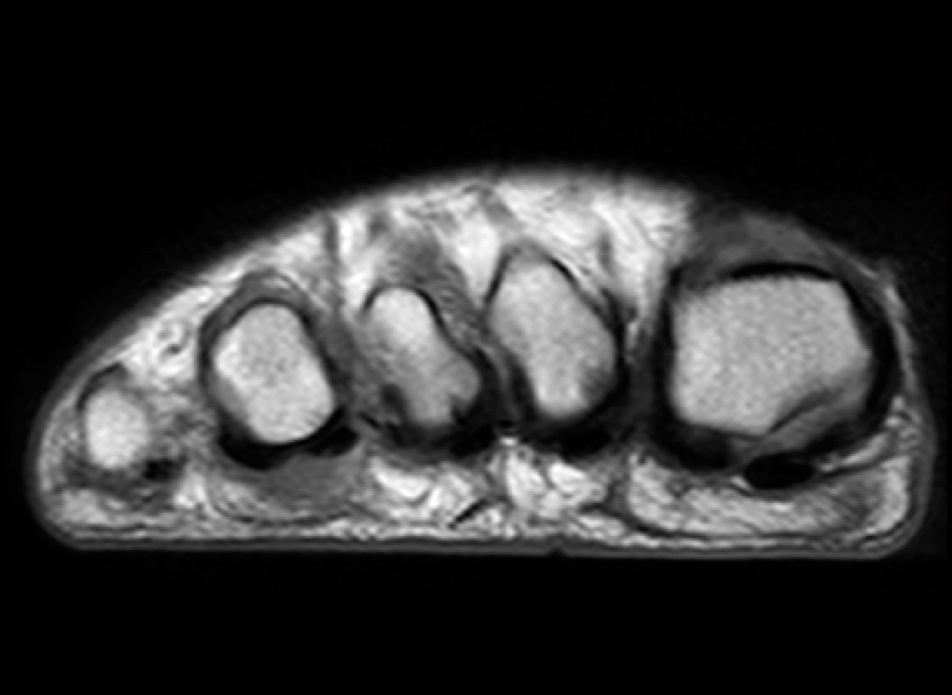

Figure 1 for case Advential bursitis

Figure 1